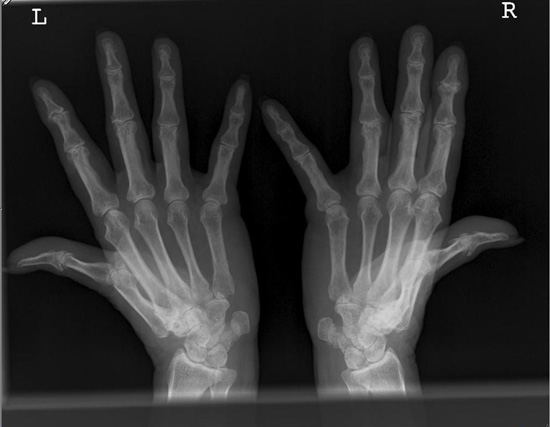

Norgaard

norgaard.jpg

Das Grundgelenk des rechten Daumens ist in der Norgaard-Aufnahme nicht gut einsehbar. Es wird teils vom Metacarpalen 2 überlagert. Die Daumen wurden bzw. könnten nicht genügend nach außen gestreckt werden.

Abhilfe

Bei solchen Patienten, die Probleme haben die Daumen mit eigener Kraft nach außen zu "biegen", sollte man mit Klebestreifen (Leukosilk) nachhelfen und die Daumen nach außen ziehen. Aber auch nur so weit wie es der Patient toleriert.